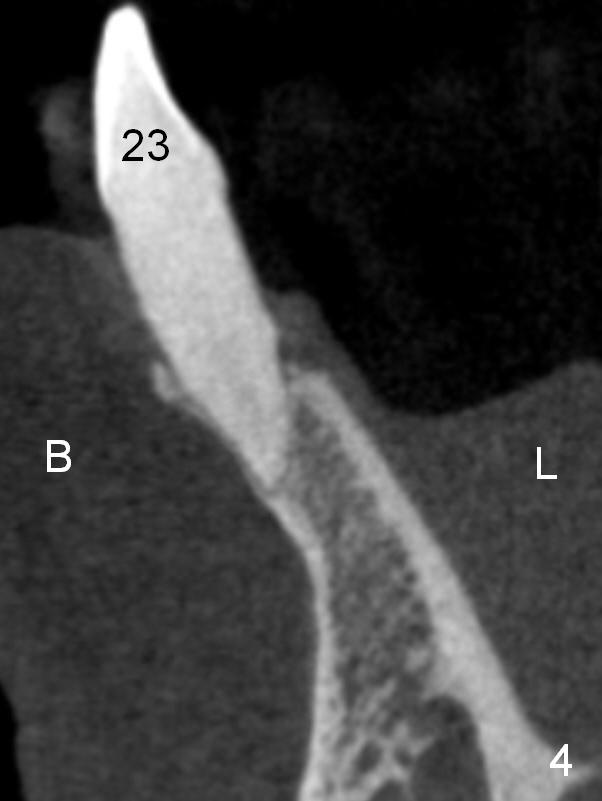

A 74-year-old man has several missing teeth (Fig.1).  His 1st goal is to replace the lower left lateral incisor (Fig.2).  The residual root has an apical lesion (Fig.3 *).  To describe intraop findings, a CT image of a different patient is used (Fig.4 coronal section; B: buccal; L: lingual).  After extraction, the buccal plate is found to be thin and low (Fig.5 arrowheads).  A 1.5 mm pilot drill (Fig.6 red line) is used to initiate osteotomy in the lingual plate of the socket.  Once the drill penetrates the lingual plate, the trajectory changes and the depth is 17 mm from the gingival margin (Fig.7).  A PA is taken (Fig.8); it appears that the osteotomy can be extended more apically.  When the pilot drill extends to 20 mm, there is sudden empty feeling.  The lingual plate has perforated (Fig.9).  A new osteotomy is established buccally (Fig.10 pink).  To avoid buccal plate perforation, especially in the buccal undercut area (>), the coronal end of the drill has to be tilted buccally (<--).  An angled abutment (3x20 mm, 15°) is placed (Fig.11,12).  The abutment is modified (Fig.13,14) to accommodate an immediate provisional (Fig.15,16 P).  Perio dressing is to be applied to prevent the bone graft from getting dislodged buccally (Fig.15).  The dressing is in place 7 days postop (Fig.17).